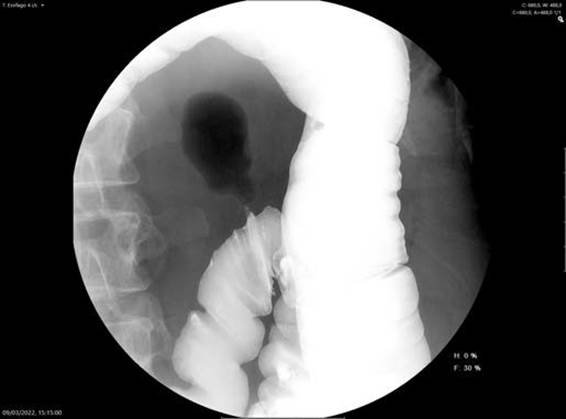

de interés. Se realizó un colon por enema en el que

se apreció la misma configuración de gas intraabdominal (Fig. 2).

Figura 2. Colon por enema. La estrecha luz del cuello del divertículo no permite el paso del contraste, aunque se aprecia la presencia de gas en su interior.